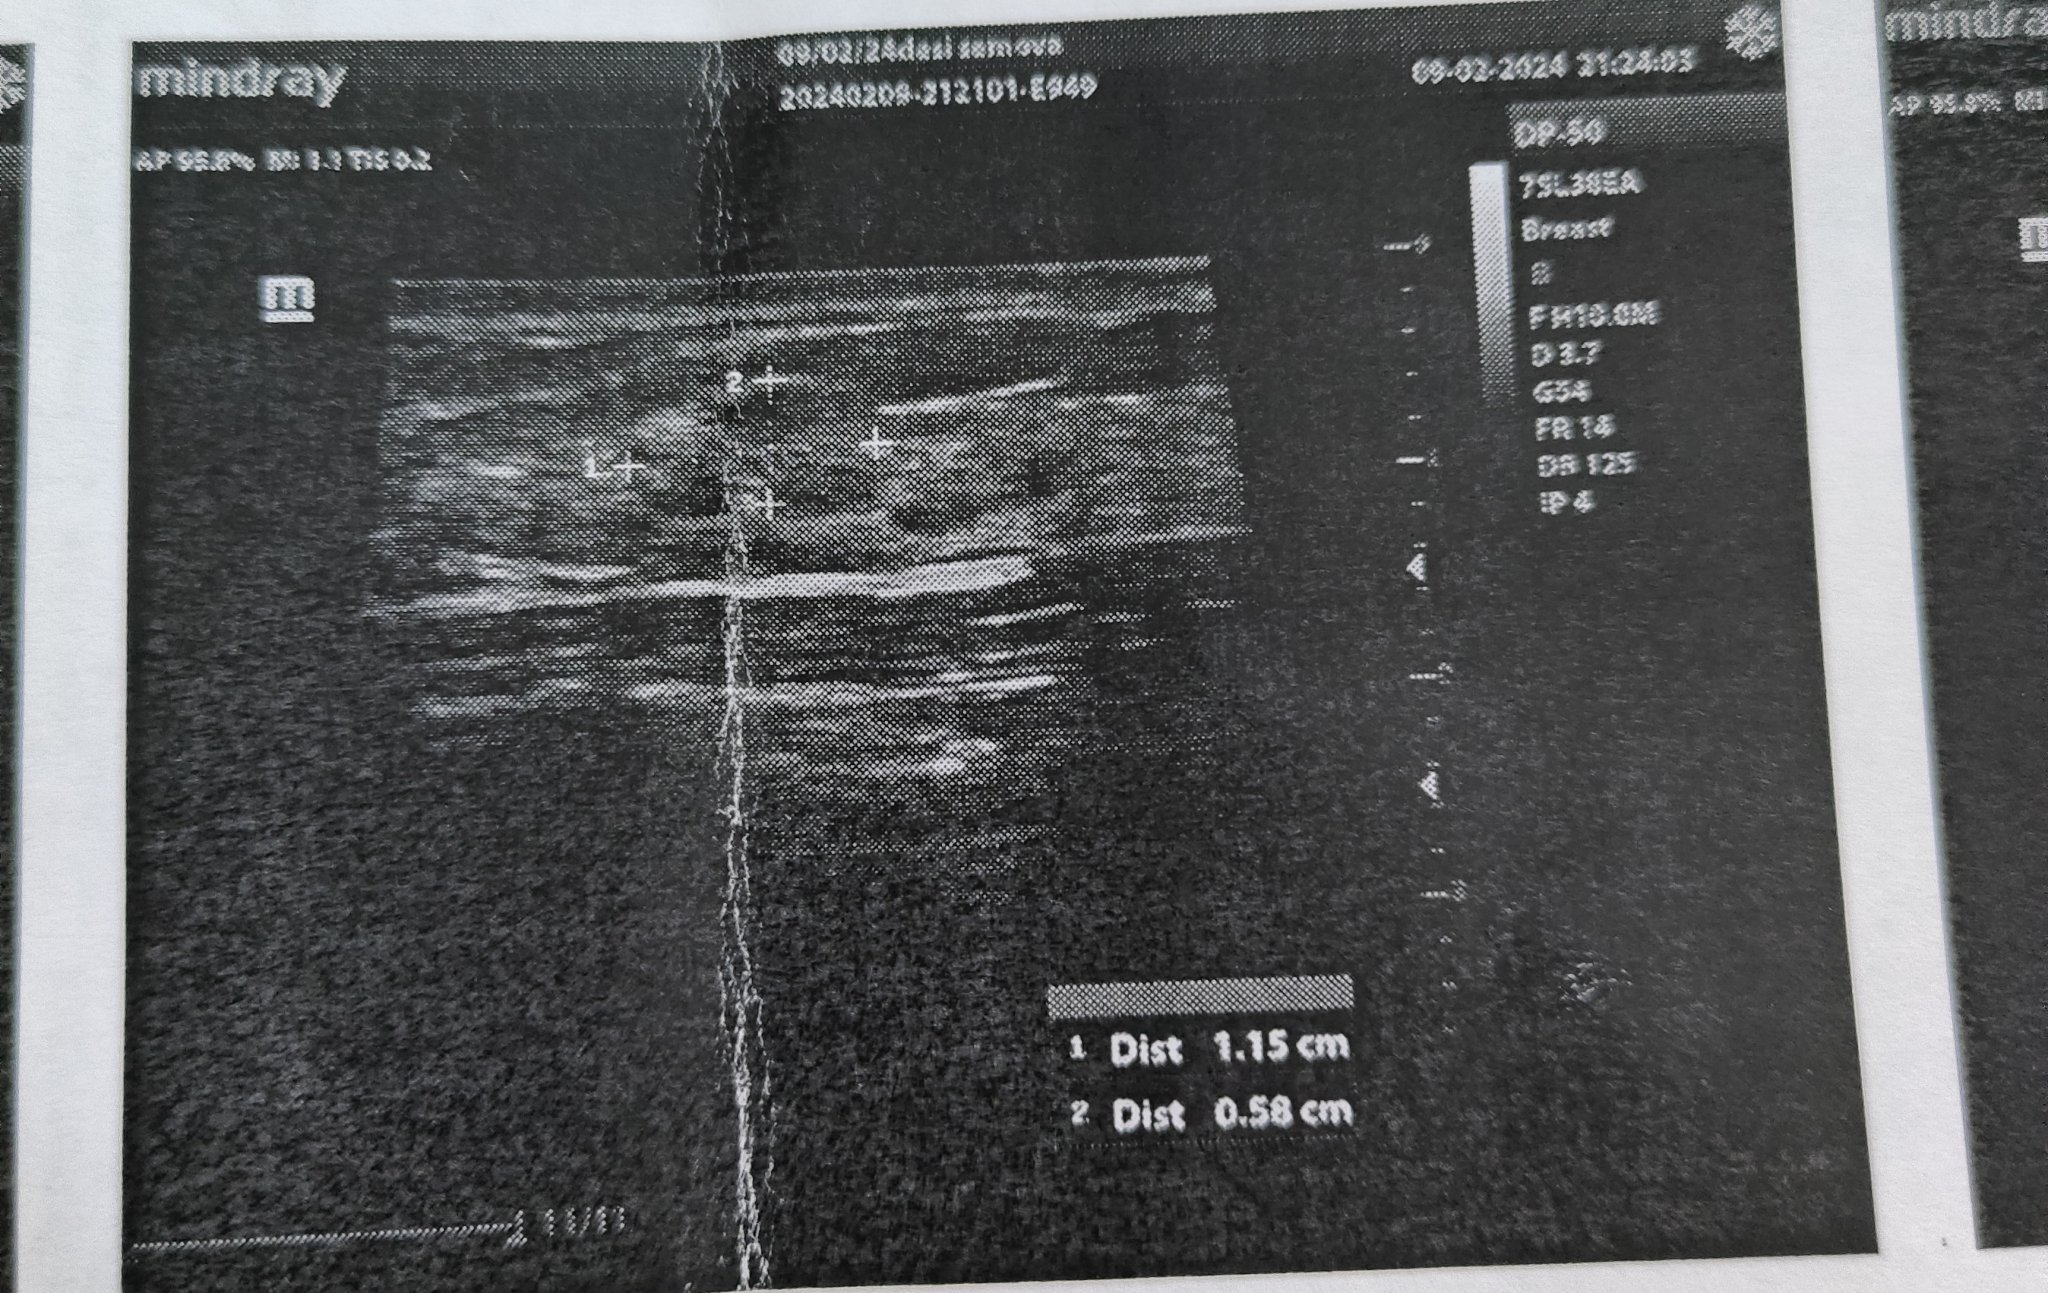

Фиброаденомът е най-често срещаният доброкачествен тумор на гърдата при жени преди менструация. Това е плътна, добре дефинирана доброкачествена туморна маса, съставена от епидермални и мезенхимни компоненти на лобулите. Честотата му варира от 15 до 23%, като по-често се среща при чернокожи жени. Обикновено се диагностицира между 25-35-годишна възраст. Фиброаденомът е доброкачествен тумор, който се развива в гръдната тъкан. Обикновено се усеща като меко, подвижно топче и може да варира по размер. Те са често срещани при жените и могат да се променят по размер поради хормонални промени, като бременност или кърмене.